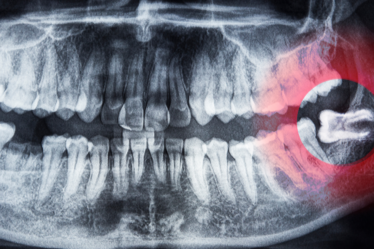

Sendo assim, o diagnóstico começa com um planejamento digital em 3D, onde o cirurgião simula os movimentos ósseos no computador antes de iniciar o procedimento, garantindo total previsibilidade.